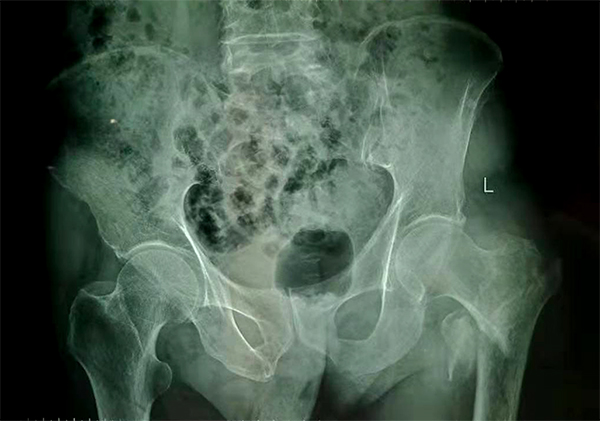

經(jīng)檢查拍片診斷為左股骨粗隆間粉碎性骨折,收入骨科住院,張爺爺既往有“2型糖尿病”病史10余年,還有“腦梗塞”病史5年,導(dǎo)致左側(cè)肢體偏癱。

手術(shù)前

手術(shù)后

9月10日上午,骨科順利完成張爺爺?shù)淖蠊晒谴致¢g骨折髓內(nèi)釘內(nèi)固定術(shù)。手術(shù)過程中麻醉平穩(wěn),術(shù)中出血量少,骨折手術(shù)時(shí)間持續(xù)一個(gè)多小時(shí)。